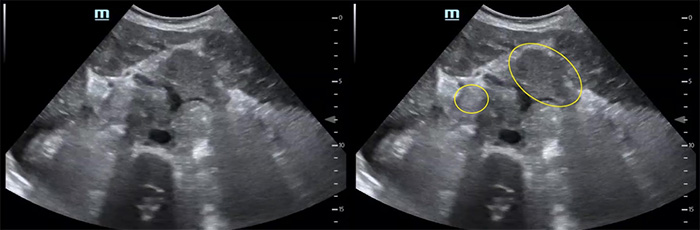

Figure 6. Numerous periaortic lymph nodes

Video 8. Proximal aorta with multiple enlarged periaortic lymph nodes

- Periaortic lymph nodes greater than 1cm: OR = 2.6, 21 PPV = 69%, NPV= 27%18

- Periaortic lymph nodes can be hard to identify. As they enlarge, they are easier to see and often lose their central hyperechoic region (hilum). As you scan through a lymph node, they will appear to grow then shrink because of their spherical shape.